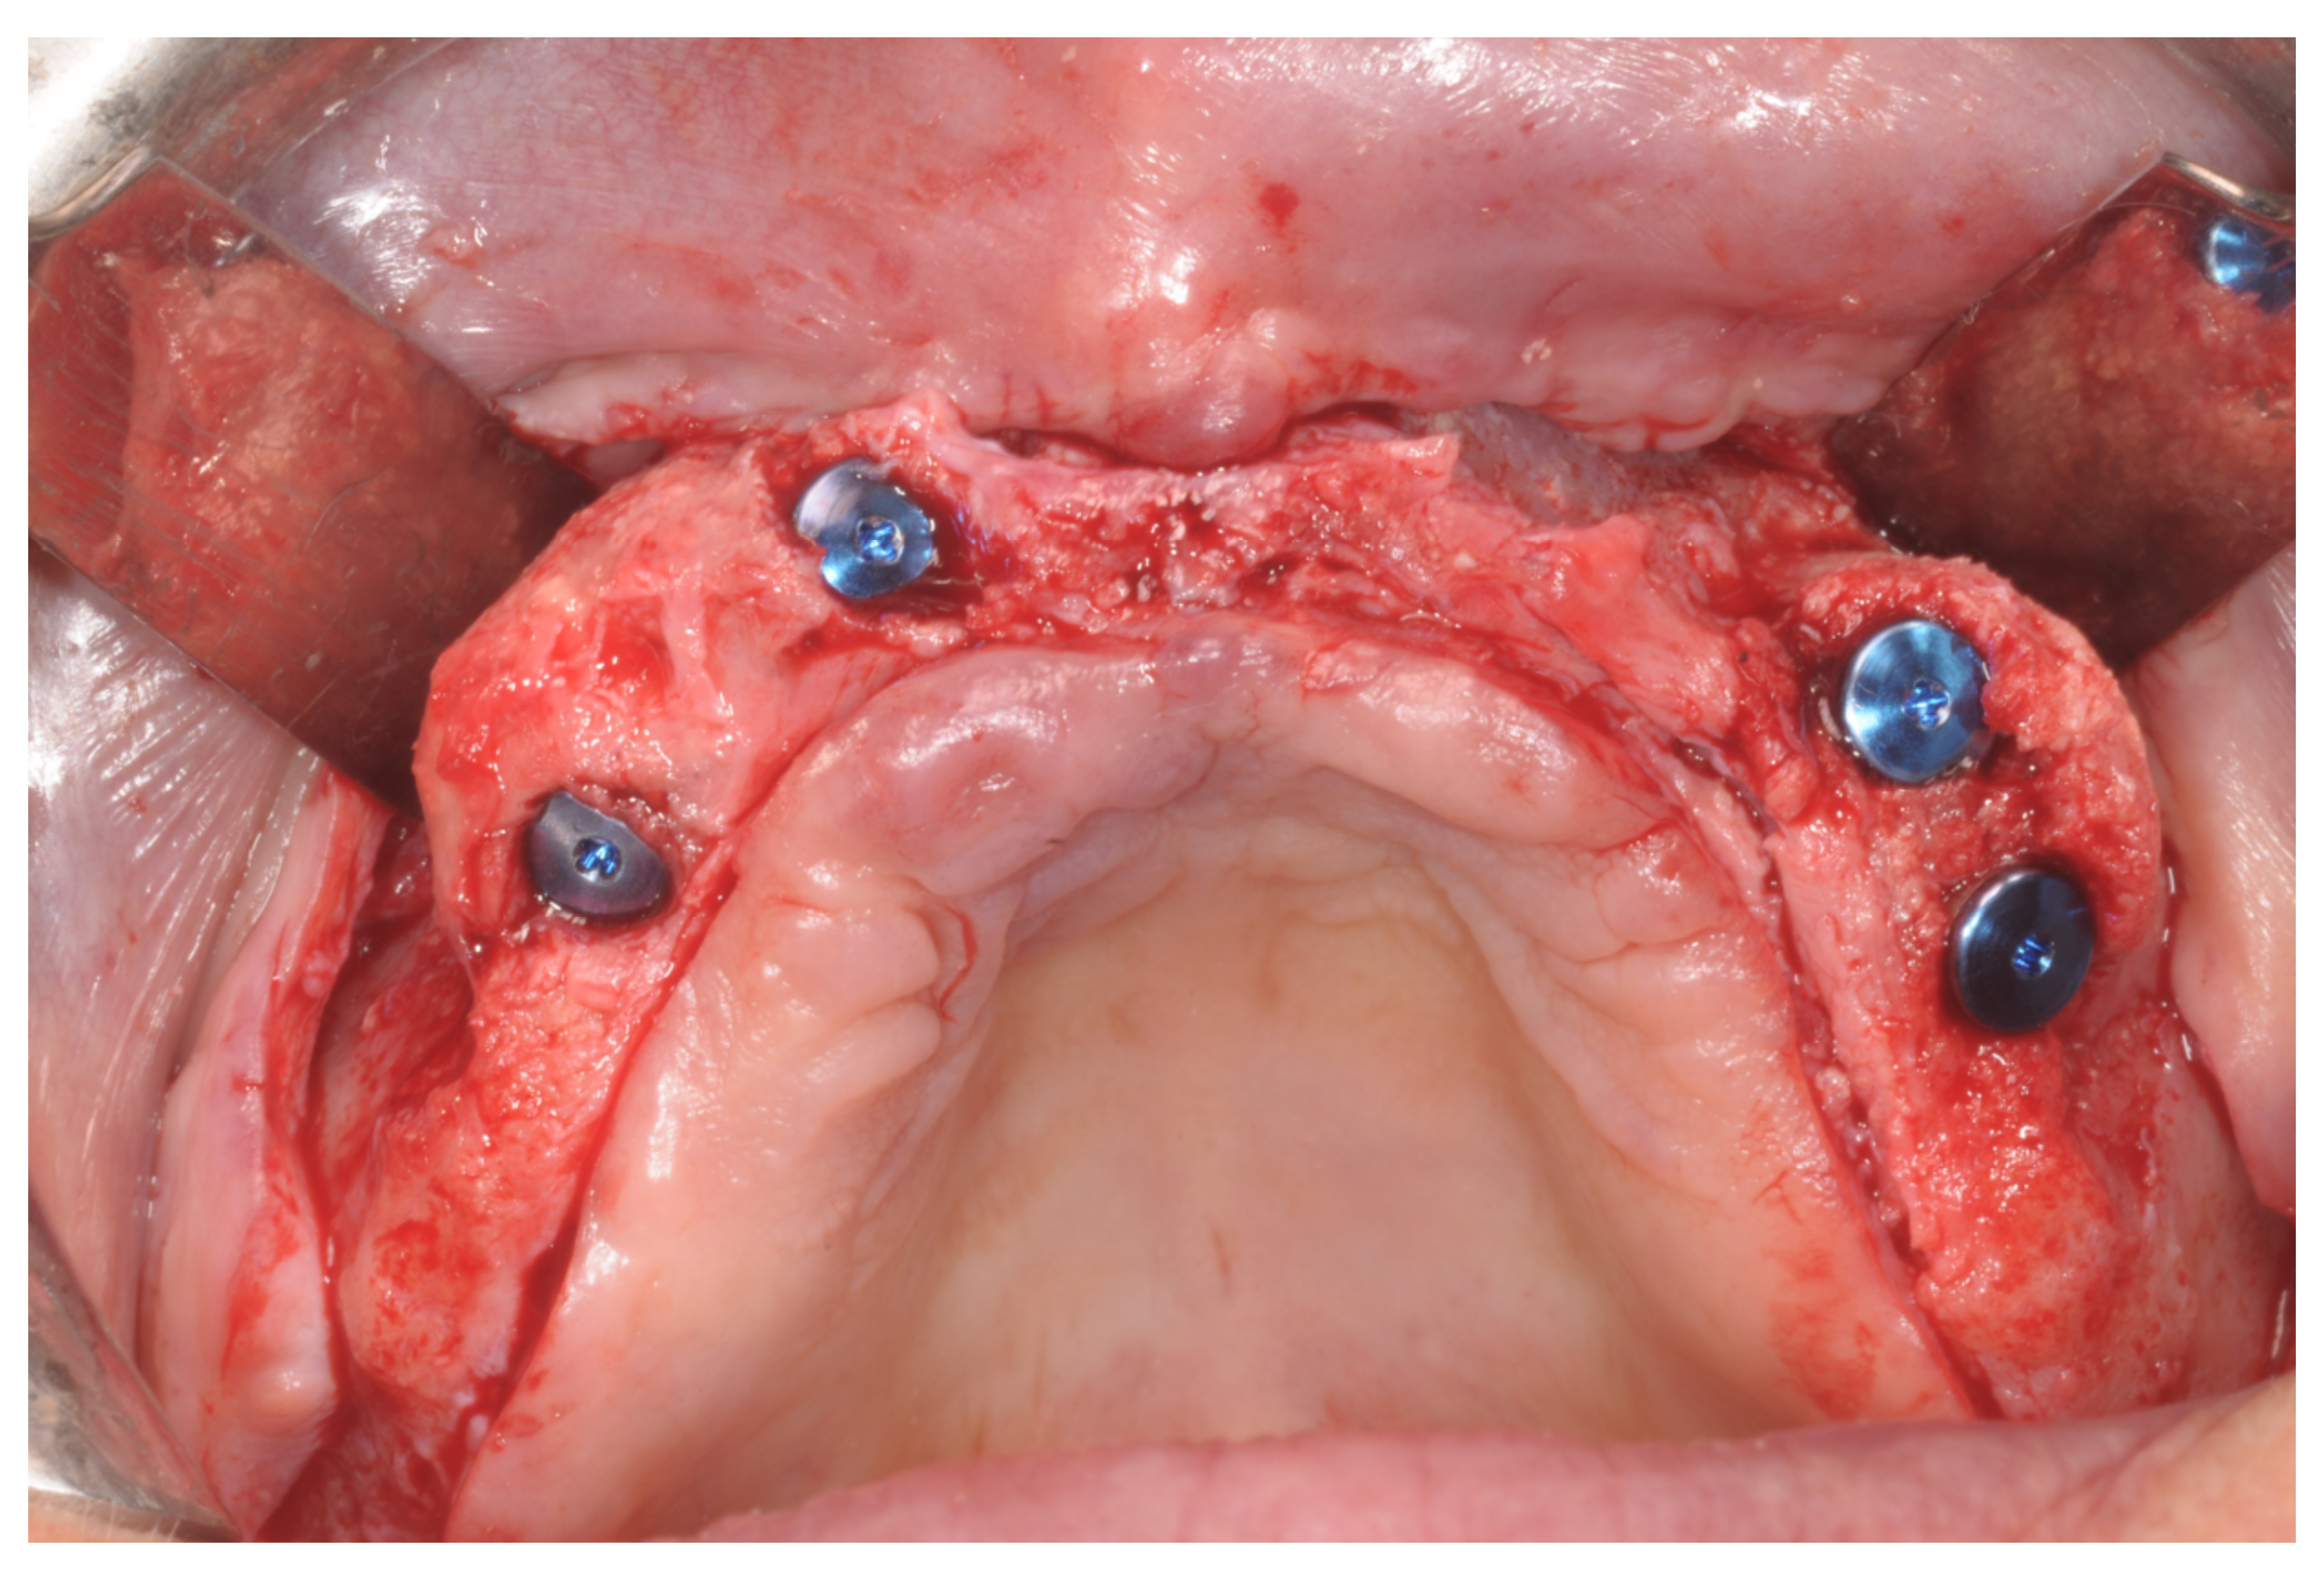

Figure 6. Surgical exposure of the augmented area 9 months after GBR.

Figure 7. Placement of the dental implants.

At this point, a non-resorbable high-density PTFE barrier (Cytoplast TXT-200, Osteogenics Biomedical, Lubbock, TX, USA) was designed on the basis of the bone defect shape and was distally blocked on the bone by two titanium pins (Kalos, Nike, Orbetello, Italy). A mixture of 50% autogenous bone harvested from the mandibular ramus with the use of a scraper and 50% inorganic bovine bone (Bio-Oss, Geistlich, Wolhusen, Switzerland) was placed in the recipient site and the membrane was pulled and blocked on the bone with two mesial pins. With this particular, and innovative, non-resorbable membrane management, the graft was compressed and fixed on the recipient bed (Figure 9, Figure 10 and Figure 11). The occlusal portion of the graft was then covered with a layer of a collagen resorbable barrier (Bio-Gide, Geistlich) (Figure 12) and peri-osteal incisions were performed to make the flap passive.

Figure 9. Occlusal view after implant placement.